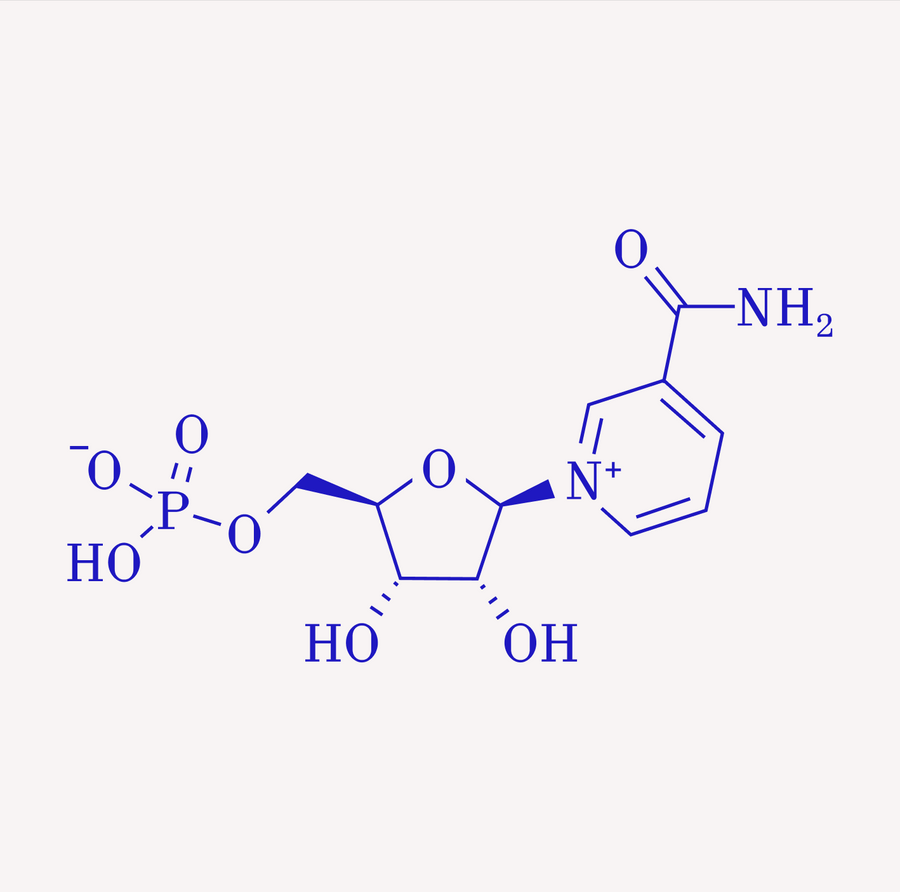

NMN

Restores energy and repair pathways in skin cells.

Vitamin C + Niacinamide

Brighten tone, strengthen barrier, and protect against environmental stressors.